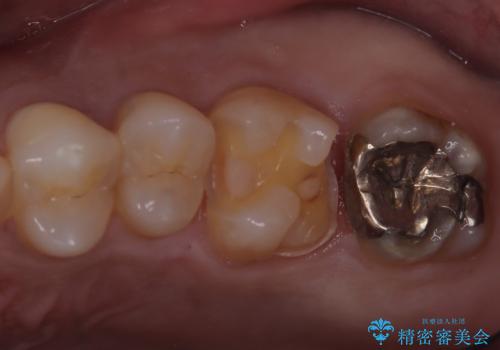

【セラミックインレー】歯科検診にて虫歯発見。

- 定期健診にて虫歯を見つけたためセラミックインレーにて修復しました。